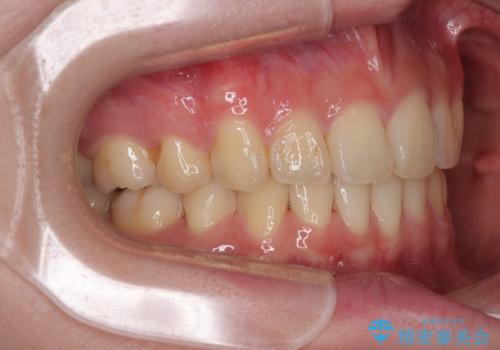

- 下顎の前歯が上顎の歯肉に咬みこむくらいに突出した上顎前歯を気にして来院された患者様です。

口元の突出感はないものの、上顎前歯が前方に傾斜して突出しており、前後に大きなズレがあり非常に深い咬み合わせとなっていました。